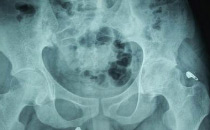

髋关节

例子

病症描述:(图1)腰椎1-5呈竹节样表现,(图2)髋关节钙化.脊柱弯曲困难间隙变小.(图3)髋关节间隙变小钙化。